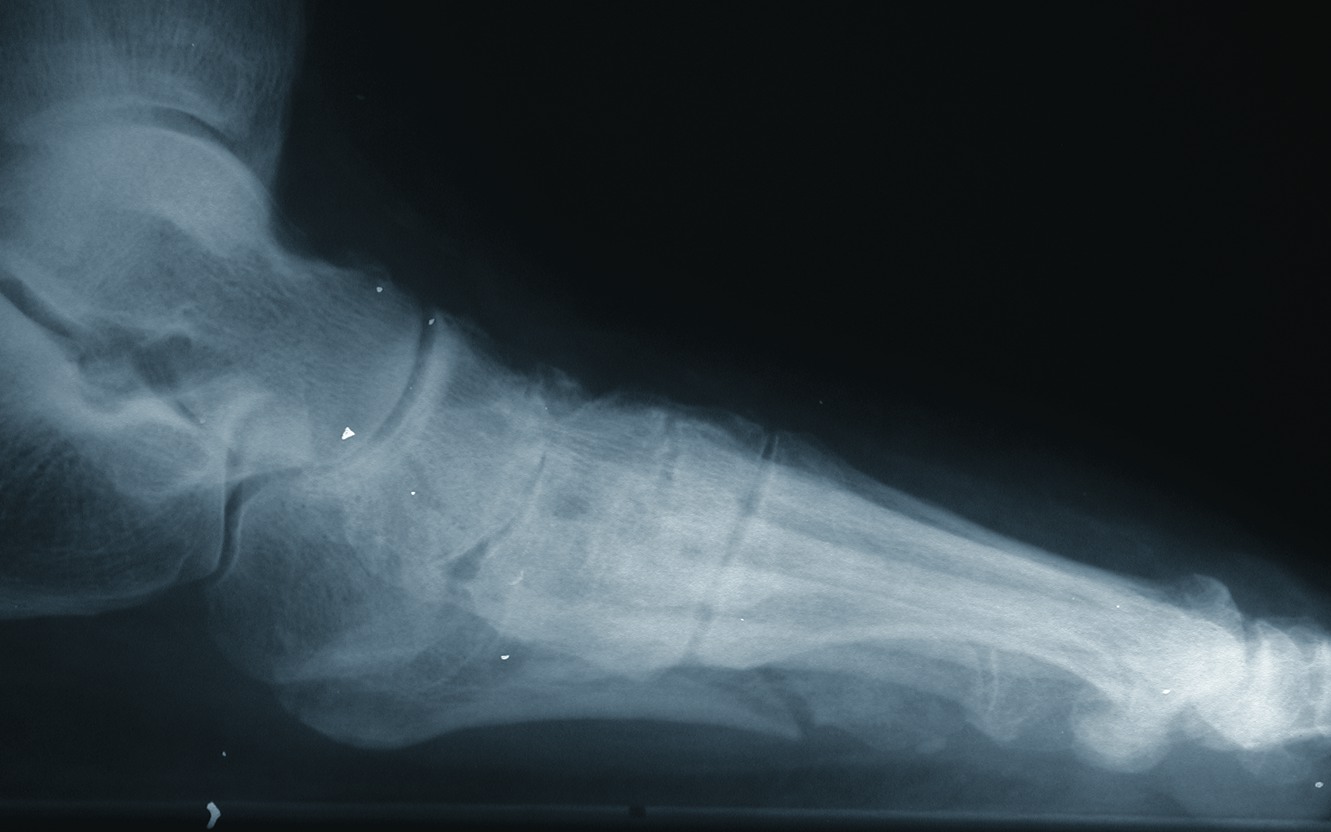

In the face of diabetes, joint stiffness and immobility can result from the glycosylation of soft tissues. This phenomenon is known as cheiroarthropathy.14,15 One would find this soft tissue glycosylation proportionate to the severity of diabetes. Clinicians can predict cheiroarthropathy based upon hemoglobin (Hgb) A1C levels. For every unit above eight, there is an increased risk of joint immobility by 250 percent.14 This type of joint dysfunction will lead to abnormal weightbearing and further complicate the aberrant gait patterns noted in patients with peripheral neuropathy. Research has further clarified that the motor deficits associated with advanced neuropathic disease results in muscle weakness and the development of abnormal mechanics in weightbearing and gait. Abnormal biomechanics yield atypical weightbearing patterns and the development of stress phenomena in soft tissue and bone. Associated ligamentous structures can become worn and elastic properties may diminish, resulting in joint instability and fractures. Newman proposed the theory that ligamentous laxity was the earliest sign of neuropathic joint disease.16 The prevailing thinking is that this laxity is the start of a vicious cycle of subtle subluxations and dislocations that would be a prelude to spontaneous dislocations of joints. If left unchecked, this would result in fractures and subsequent reactive bone formations that have become pathoneumonic for the Charcot joint. In the case of the neuropathic patient with motor and peripheral sensory loss, the lack of epicritic sensation results in a failure to recognize weakness, injury or insufficiencies of soft tissue or bone. This combined motor sensory dysfunction sets the stage for even trivial trauma to incite a dramatic propagation of inflammation, soft tissue hyperemia, resorptive bone destruction and complete loss of structural integrity that is often the harbinger of limb loss. In reviewing the historic literature, Peltier points out that the classic article written by Charcot did not correlate the development of a Charcot joint to diabetes but emphasized its relationship to locomotor ataxia.17,18 Coupling this with the fact that we are learning more and more about the effects of non-insulin dependent diabetes mellitus (NIDDM) on the dynamics of the musculoskeletal system, it stands to reason that we may be seeing more injury and reports of Charcot joint development as the number of patients with diabetes has increased in epidemic proportions over time.19 Neuropathic joints come in two varieties: hypertrophic and atrophic.5 In the wake of hypertrophic bone destruction, one will see subchondral cystic degeneration, cortical erosions, joint space narrowing, subluxations and dislocations with sclerotic changes, fragmentation of bone and heterotopic bone formations. In regard to these abnormal bone changes, clinicians typically see them in the lower extremities anywhere from the metatarsophalangeal joints to the ankle. While the Lisfranc joint is the most commonly afflicted, midfoot, rearfoot and ankle destruction is not uncommon. When it comes to atrophic bone destruction, physicians usually see this condition in the upper extremities and it typically involves patterns of resorptive change in the joint margins. For the most part, management of the neuropathic joint is guided by radiographic changes clinicians see in serial X-rays. One can cross-correlate the clinical staging of disease with radiographic changes. Immediate treatment includes the benefit of offloading the lower extremity and extensive patient education.